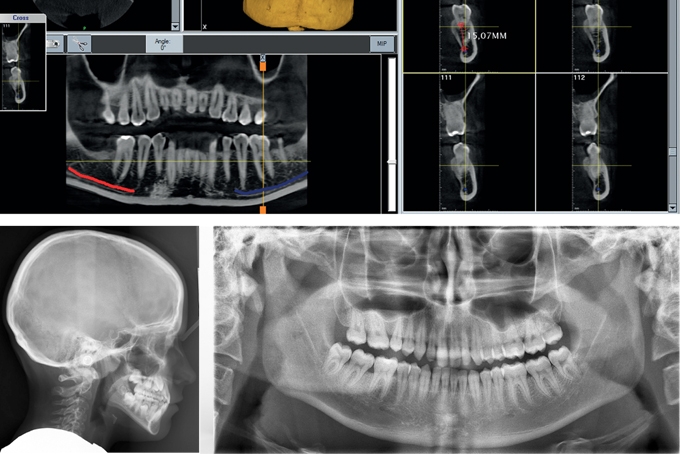

X.VIEW.3D della Trident è un sistema volumerico Cone Beam, per la diagnostica 3D/2D per la radiologia odontoiatrica. X-VIEW-3D è a tutti gli effetti un sistema multifunzionale tre in uno. Progettato per essere una CBCT si è voluto mantenere la possibilità di fare anche delle Panoramiche/teleradiografie2D. X-VIEW-3D rappresenta la tecnologia di ultima generazione e per i suoi contenuti offre soluzioni diagnostiche adatte a soddisfare le richieste più esigenti. Il flat panel con tecnologia CMOS offre un'area attiva di 13 cmx13 cm con un field of view effettivo di 8,5 cm x 8,5 cm il volume acquisito conterrà le due arcate dentarie nel suo completo e le parti anatomiche di interesse , seni paranasali compresi. Il sensore CMOS ha un pixel di 100 μ garantendo in alta risoluzione un voxel di 166 μ. Un'ideale definizione per una diagnosi immediata. Inoltre è bene sapere che i 14 bit del sensore garantiscono fino a 16384 livelli di grigio. Per quanto riguarda le applicazioni 2D x.view nella panoramica vi offre il multilayer: "Dopo avere acquisito la pano nel monitor del PC in Dotazione vi verranno proposte tre immagini, la prima sarà quella primaria che segue la normale linea mediana dell'arcata dentaria, inoltre avrete due immagini panoramiche, una di due mm più spostata in zona Linguale e l'altra di 2 mm in più verso la zona vestibolare. Questo UP GRADE vi permette di vedere sempre tutta la dentizione in una perfetta messa a fuoco anche se i denti non sono perfettamente allineati tra loro. Altra grande prestazione di x-view nel 2D è la teleradiografia Single Shot 24cmx30 cm con il suo sensore dedicato Flat Panel phosphor plate con lettore incorporato. Grande Formato con bassa dose di raggi e tempo di esposizione da 1 a 2 secondi. Concludiamo con gli Algoritmi di ricostruzione utilizzati che migliorano la definizione e la qualità delle immagini permettendo di individuare anche i più piccoli particolari anatomici l'insieme degli Algoritmi e la tecnologia permettono di ridurre l'effetto scatering di metalli sull'immagine 3D, evitando artefatti evidenziati come strisce ed ombre a scapito di un buon risultato diagnostico. L'interazione degli algoritmi velocizza la ricostruzione dell'immagine acquisita infatti la ricostruzione di un volume 8,5 cm x8,5 cm la si ottiene in meno di 10 secondi.